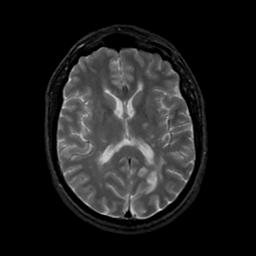

MR Study #16, June 23, 1991 -- Slice #28